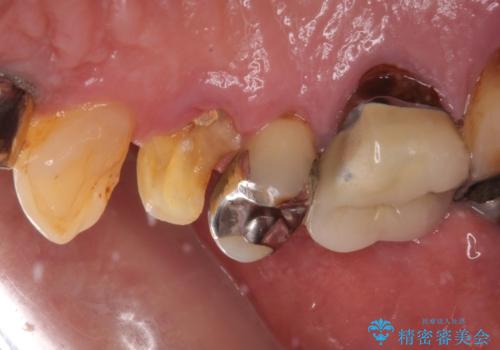

当院での根管治療および歯周外科治療を併用した保存療法、並びに1DAYインプラントによる短期間インプラント治療の双方をご説明し、即日でインプラント治療を選択されました。

仮歯を用意した上で、抜歯即時埋入・即時荷重インプラントによる補綴治療を行うこととしました。

従来のインプラント治療について回った3回の外科手術や半年移動の治療期間とは無縁の、短期間治療を達成することができました。